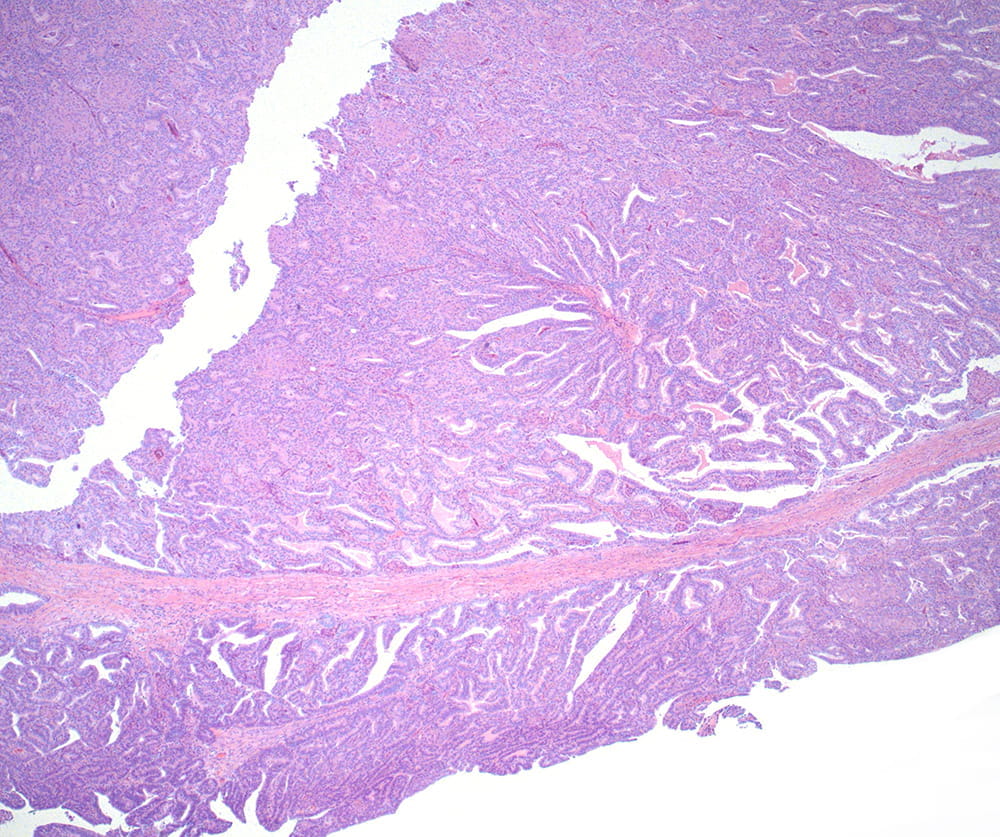

Figure 1: H&E, 4x- Ovarian carcinoma with glandular growth.

Histologic examination of the ovarian mass reveals an adenocarcinoma characterized by a biphasic architecture, consisting of both glandular and corded/hyalinized components. These two morphologic patterns merge seamlessly and share similar cytologic features. Notably, there is squamous and spindle cell differentiation throughout the tumor.